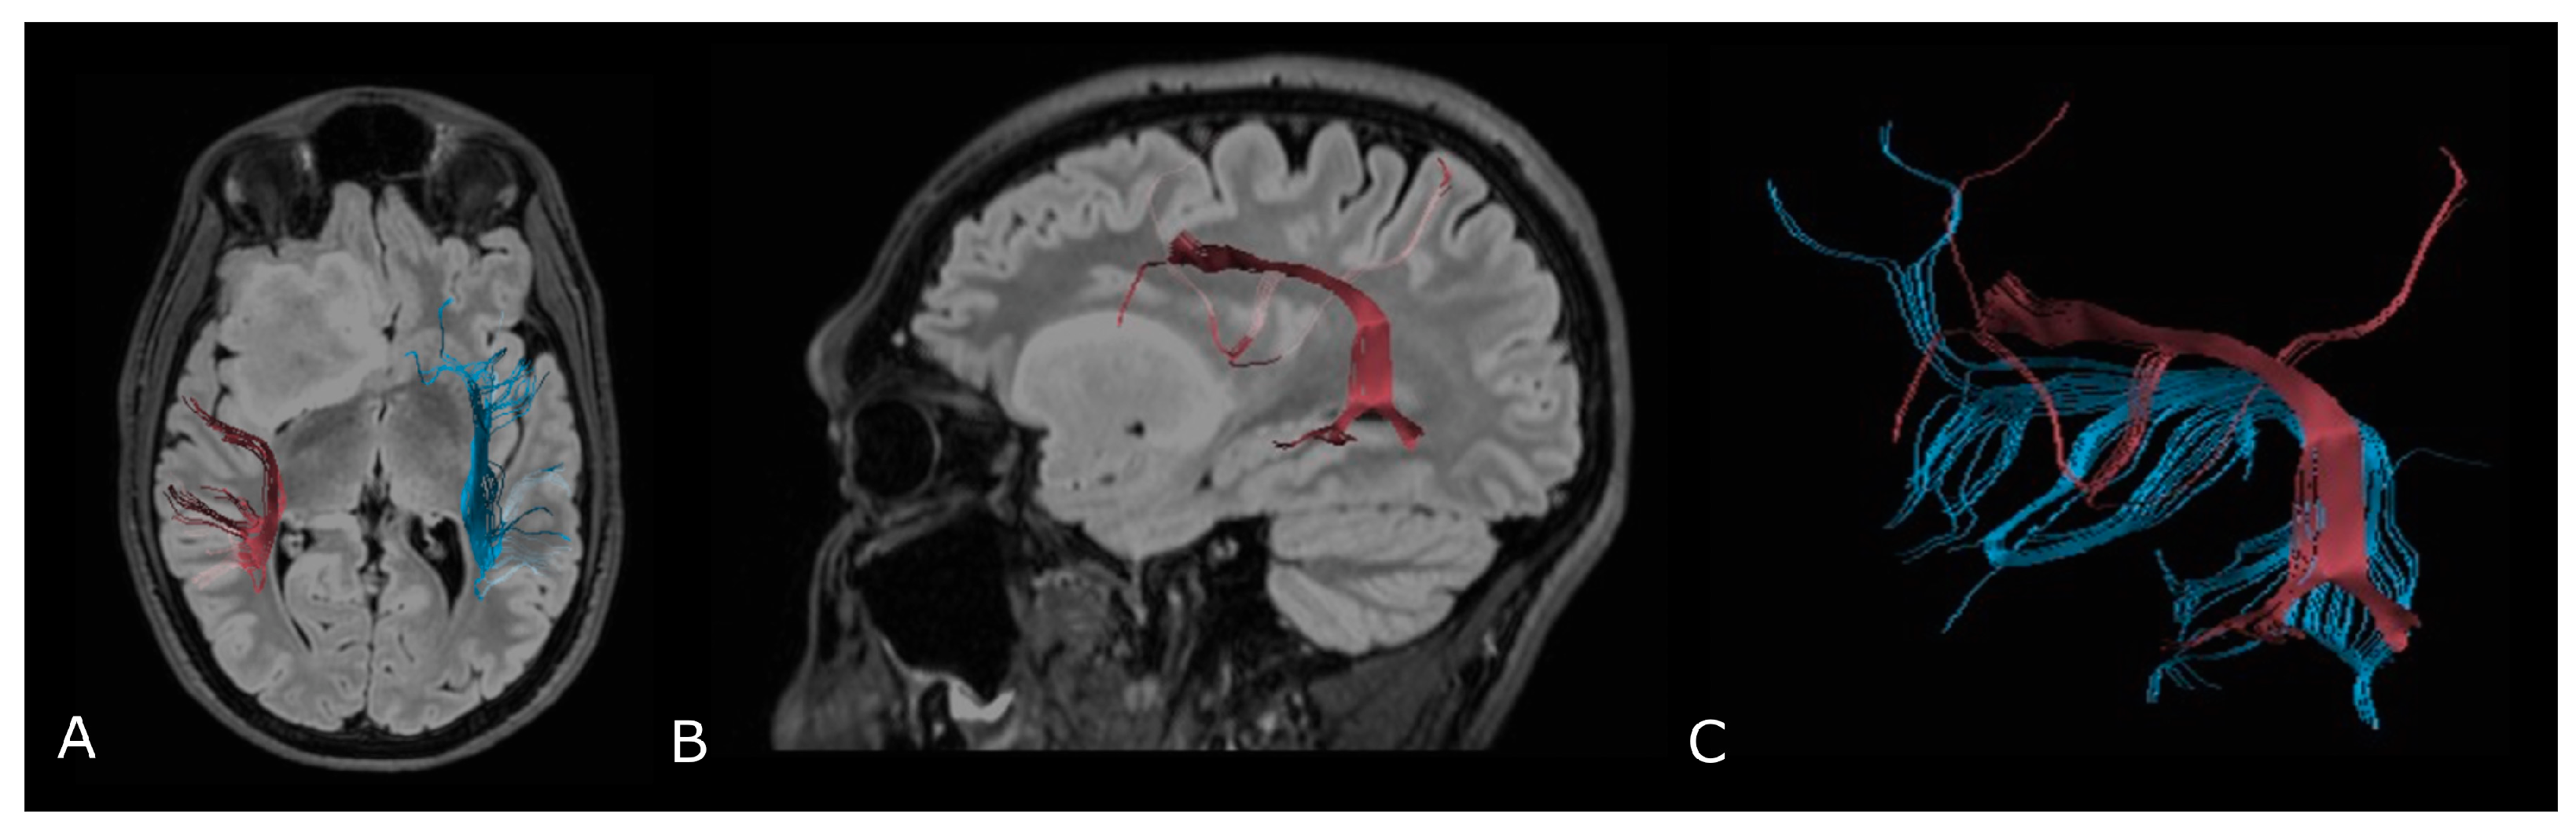

Figure 6.

Diffusion Tensor Imaging: (A) normal FA map without any directional information; (B) Combined FA and directional map. Colors indicate directions as follows: red, left-right; green, anteroposterior; blue, superior-inferior. Brightness is proportional to FA; and (C) 3D visualization of normal corticospinal tracts.

Figure 7.

Tractographic reconstruction of arcuate fasciculi. DTI of the direct pathway of both arcuate fasciculi (AF) fused with anatomic axial (A); and sagittal (B) FLAIR images. The right AF on the affected side is superiorly and posteriorly displaced by an IDH-mut frontal-temporal-insular astrocytoma; (C) 3D rendering of both arcuate fasciculi.